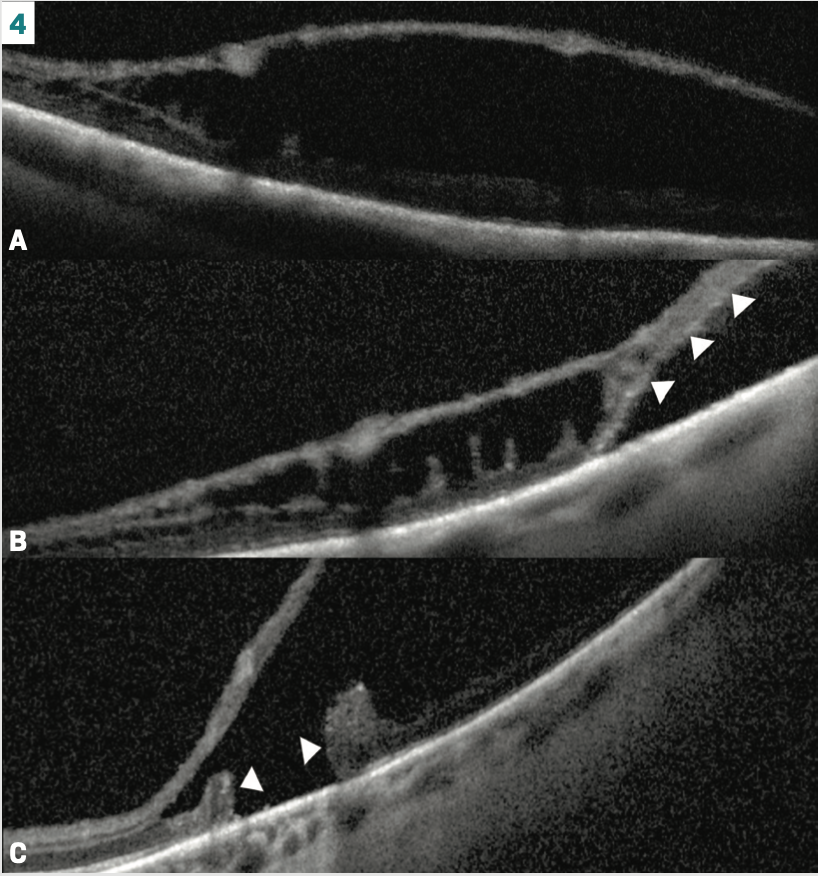

Not only are retinoschises more common, so are schisis detachments

After employing P-OCTs, there appears to be a greater number of clinically undetected retinoschises. The same applies to a schisis detachment, which is when an outer layer break allows intracystic fluid to reach the subretinal space, causing a localized retinal detachment (Figure 4).8 In fact, over 15% of presumed retinoschises by clinical evaluation showed a retinal detachment with P-OCT.9 Schisis detachments mostly remain stable with outer layer holes alone vs when outer and inner layer holes are present.6 The reason here is that there is a limited amount of intracystic fluid that can reach the subretinal space with an outer layer hole. However, an inner and outer layer hole opens the area up to the more voluminous vitreous fluid. Fortunately, the incidence of inner layer holes is low (4%), with outer layer holes having a prevalence of up to 17%.6